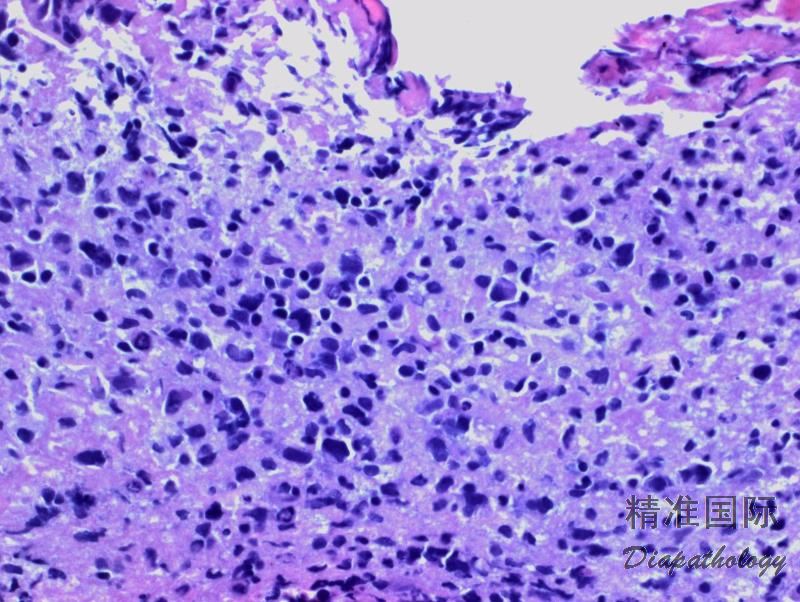

肿瘤细胞呈现弥漫浸润性生长,边界模糊;也可呈现斑片状或血管中心性浸润 (特征性浸润血管周围间隙)。可见单个细胞或地图样坏死。

肿瘤细胞中到大,核圆、椭圆、不规则或多形,可与中心母细胞或免疫母细胞较相似,常混有反应性小淋巴细胞、巨噬细胞和胶质细胞。